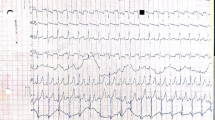

A full term, female infant was born to a G1P0 mother whose fetal ultrasound was concerning for HCM at 27 weeks gestation. The newborn had a normal clinical exam with normal muscular tone, and postnatal ECG showed mild hypertrophy of the interventricular septum (Fig. 1a). Electrocardiogram (EKG) was notable for a very short PR interval, ventricular pre-excitation, and high ventricular voltages (Fig. 1b). At 2 days of life, GAA enzyme level was low at 1.5 nmol/mg protein (normal 6–37 nmol/mg protein) on leukocyte-based assayat a local lab, urine (E)-hex-4-en-1-yl butyrate (HEX4) was elevated at 34 nmol/mol (normal <19 nmol/mol creatinine), and creatinine kinase was elevated at 2261 IU/L (normal 38–174 IU/L). Given this presentation, suspicion for IOPD was high. Biopsies of skeletal muscle and skin were obtained, and ERT with alglucosidase alfa was promptly started while waiting for biopsy results to determine CRIM status.

A full-term female infant had wheezing at 5 weeks of age and failed bronchodilator therapy for presumed reactive airway disease. At 11 weeks of age, she presented with more severe wheezing at her pediatrician’s office, which prompted referral to the emergency room. Chest X-ray showed severe cardiomegaly, and an ECG demonstrated severe biventricular hypertrophy, severe mitral regurgitation, and moderate tricuspid regurgitation (Fig. 2a). EKG showed biventricular hypertrophy, a short PR interval, and interventricular conduction delay (Fig. 2b). She was transferred to the cardiac intensive care unit where she was started on milrinone, oxygen, and furosemide for heart failure. She developed persistent ventricular ectopy, which required a lidocaine infusion. Suspicion for IOPD was high, but blood GAA enzyme activity level was normal at 15.8 pmol/punch/h (normal ≥ 10.88 pmol/punch/h), and GAA gene sequencing and urine HEX4 were also normal. Because of the care team’s experience with PRKAG2 cardiac syndrome in the patient described in case 1, this was high in the differential diagnosis. Blood was sent for a commercially available familial HCM panel, which showed a disease-causing mutation in the PRKAG2 gene (c.1592G > A p. Arg531Gln). The patient had persistent arrhythmias and poor cardiac function requiring high-dose inotropy and was therefore listed for cardiac transplant at 3 months of age. She remained in the hospital on milrinone infusion awaiting transplant, but her clinical status continued to decline. At 4 months of age, she had an episode of cardiac arrest requiring extracorporeal membrane oxygenation (ECMO) cannulation. She then developed severe renal dysfunction, a large right intracerebral hemorrhage presumably from anticoagulation required for ECMO, and was unable to recover any meaningful cardiac function. The decision was made by the family and healthcare team to withdraw support, and the patient died at 4 months of age. No muscle tissue biopsy or autopsy was performed.

Our case series highlights the challenges of diagnosing PRKAG2 in infancy due to varying degrees of disease severity and progression. Similar to the three previously described cases with p. Arg531Gln mutation in PRKAG2 (Burwinkel et al. 2005), the patient in case 2 had severe HCM and heart failure at 11 weeks of age and succumbed at 4 months of age, which supports the idea that this particular mutation leads to a severe phenotype. Case 1 was unique in that HCM was noted prenatally, but postnatal ECG showed only mild hypertrophy of the interventricular septum (Fig. 1a), which resolved months later. She has thickened mitral valve leaflets with shortened chordae and moderate mitral regurgitation and remains clinically stable on captopril, with no overt muscle weakness and experiencing normal development. While this cardiac phenotype has not been described in other PRKAG2 patients, interestingly, in vitro work studying this novel PRKAG2 mutation (c.1423A > G p. Lys475Glu) suggests an alteration in mammalian target of rapamycin (mTOR) signaling that results in cellular hypertrophy, which can be reversed with rapamycin (Xu et al. 2017). The patient in case 3 presented with significant myopathy and mild hypertrophy of the interventricular septum that resolved while on ERT with alglucosidase alfa. Whereas myalgia during or immediately after exercise has been described in eight patients with PRKAG2 mutations (Murphy et al. 2005; Laforet et al. 2006), our case 3 is the only description of clinically significant muscle weakness and an essentially isolated skeletal myopathy without an overt cardiac phenotype. This patient improved on alglucosidase alfa ERT, and we recently described this patient’s presentation to prompt further study as to whether ERT may benefit other patients with PRKAG2 mutations (Austin et al. 2017). The use of ERT for ventricular hypertrophy in patients with PRKAG2 mutations and comparison of cardiac biopsy specimens in PRKAG2 patients with and without a cardiac phenotype could be revealing.